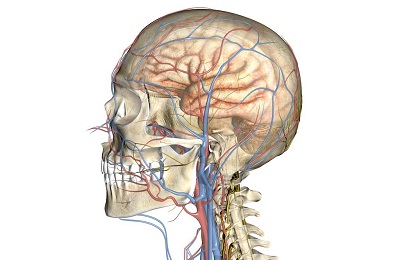

A fő feladata az emberi test vérerek -, hogy biztosítsák a teljes közlekedési vér szervekben és szövetekben.

Ehhez a test egy nagyon jól kidolgozott artériás és vénás hálózat, amely behatol minden szöveteket és szerveket. Ha problémák vannak ezzel a mechanizmussal, vannak bizonyos tünetek emberben.

- artériák és arteriolák;

- vénák és venulák;

- kapillárisok és a mikrokeringést.

Egy külön csoport izolált nyirokerek, amelyek nyirok szállítás. Ezeket a hajókat szorosan kapcsolódnak a vénás rendszer a személy. Problémák és betegségek a nyirokrendszer általában szorosan kapcsolódnak vagy a vénákban vagy a hematopoietikus rendszer.